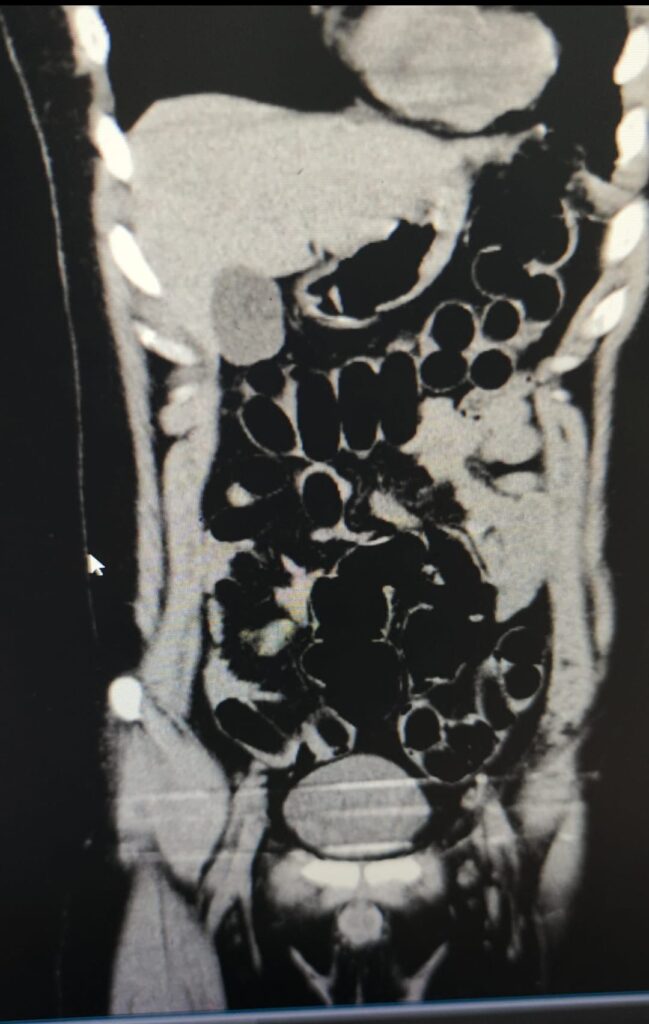

Hastanede yapılan iç beden muayenesi ve tomografi görüntüleri sonucunda şahsın midesinde uyuşturucu madde taşıdığı tespit edildi. Yapılan tespitler neticesinde, şüphelinin midesinden toplam 84 adet kapsül içerisinde daralı ağırlıkları 842 gram gelen eroin maddesi ele geçirildi.